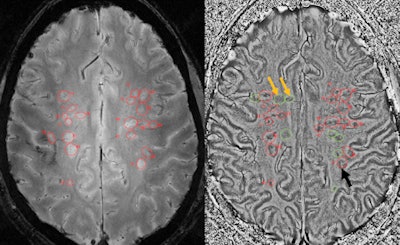

Overall, MS lesions had the highest contrast when the WHAT protocol was used, the group found.

"The high spatial resolution and excellent gray-matter/white-matter contrast allowed depicting a number of juxtacortical [adjacent to the cerebral cortex of the brain] lesions and a few gray-matter lesions," Sammet said.

The WHAT MR images also provided an "excellent depiction of perivascular spaces," Sammet added, and SWI magnitude images illustrated only 93% of the lesions seen on the white-matter attenuated sequence. He credited the difference in performance to "decreased contrast in the weakly proton density-weighted SWI images compared to white-matter attenuated images."

SWI phase images did uncover several interesting features, however. Some lesions were detected on SWI magnitude images but not on the phase images, indicating that contrast in these lesions is due to free water increase, Sammet noted. A free water increase shows as dark spots on MRI and can indicate a disorder such a multiple sclerosis.

Conversely, other MS lesions were seen on phase but not magnitude images. Sammet speculated that the phase-imaged lesions must have significant presence of paramagnetic material, such as iron, which is illuminated on MRI.

Furthermore, a dark outer ring was observed on some lesions on SWI phase images that was not visible in SWI magnitude or white-matter attenuated images. Most lesions visible on SWI magnitude and phase images were associated with venous vasculature.